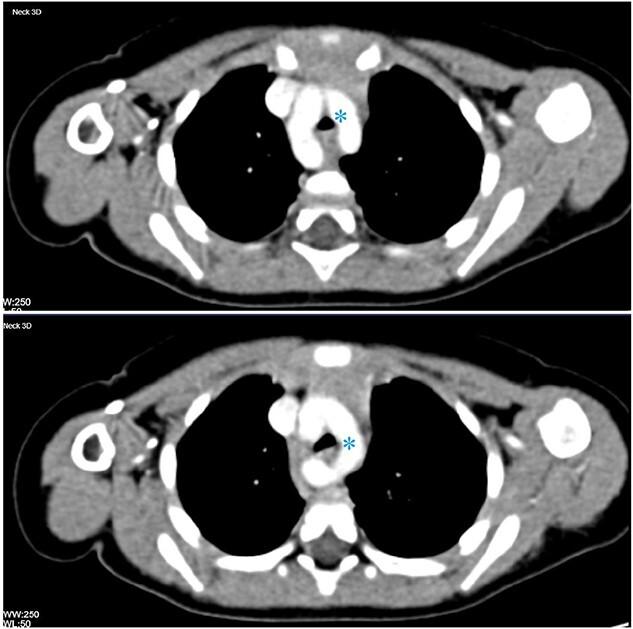

Double aortic arch: a rare cause of stridor in infants.

Double aortic arch is the most common vascular ring anomaly. It usually presents with symptoms related to tracheal and oesophageal compression. The constricting vascular ring may lead to stridor in infants and young children, which could be mistaken for upper respiratory tract infections or foreign body aspiration. It is therefore prudent to have a high index of suspicion when evaluating cases of paediatric stridor. Contrast-enhanced computed tomography and cardiac magnetic resonance imaging are the diagnostic modalities of choice to investigate vascular rings. We report a case of a stridulous infant with a double aortic arch.